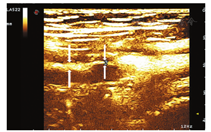

患者男,46岁,已婚。3个月前无明显诱因出现左下肢发凉、疼痛、麻木,间歇性跛行,跛行距离约100 m,休息后可缓解。无明显肿胀,皮肤无溃烂及色素沉着。既往体健,无糖尿病、高血压、脑血管病及外伤史。无饮酒、吸毒及毒物接触史。吸烟25年,平均20支/d,未戒烟。头颅CT、胸部平片、肺功能测定、血清学检测及心电图均未见异常。一般情况好,生命体征未见异常。查体:左下肢皮肤苍白,尤以膝关节以下为著,左小腿及左足皮温低,左侧股动脉搏动良好,左侧腘动脉及左侧足背动脉搏动未触及,左下肢末梢血运及感觉差。右下肢未见明显异常。生理反射存在,病理反射未引出。超声显示:左侧腘动脉走行处见长约45 mm的不规则异常回声区,挤压无明显形变,最宽处直径约12 mm,管壁不规则增厚,回声较低,其内可见不规则强回声带及不连续内膜较强回声(图1)。彩色多普勒血流显像(CDFI)示腘动脉不规则长条状血流信号,远端动脉呈小慢波。注入SonoVue造影剂后测得最窄处血流信号宽度1 mm,低回声的增厚的管壁内未见明确造影剂信号回声(图2)。超声提示:左侧腘窝所见不排除腘动脉外膜囊性病变,局部管腔不完全闭塞,建议进一步检查。随后行下肢血管CTA示左侧腘动脉管腔内见低密度充盈缺损,管腔变窄,最窄处狭窄程度约80%,狭窄长度约17.1 mm,诊断意见:左侧腘动脉低密度影,考虑血栓形成,管腔重度狭窄(图3)。患者择期手术。术中所见:左侧腘窝处可见一大小约4 cm×4 cm囊性包块,将腘动脉紧密包绕,包块近端腘动脉搏动良好,远端未见明显搏动(图4);打开囊肿外膜,可见其内充满无色透明"冻胶状"物,量约20 ml,完全清除囊肿内容物后,钝锐性结合,将囊肿从腘动脉上完整分离并切除。病理所见:破碎囊样组织,面积2 cm×1.5 cm,一侧灰白尚光滑,囊壁厚0.2~0.3 cm,另见胶冻样物。符合血管外膜囊性改变。